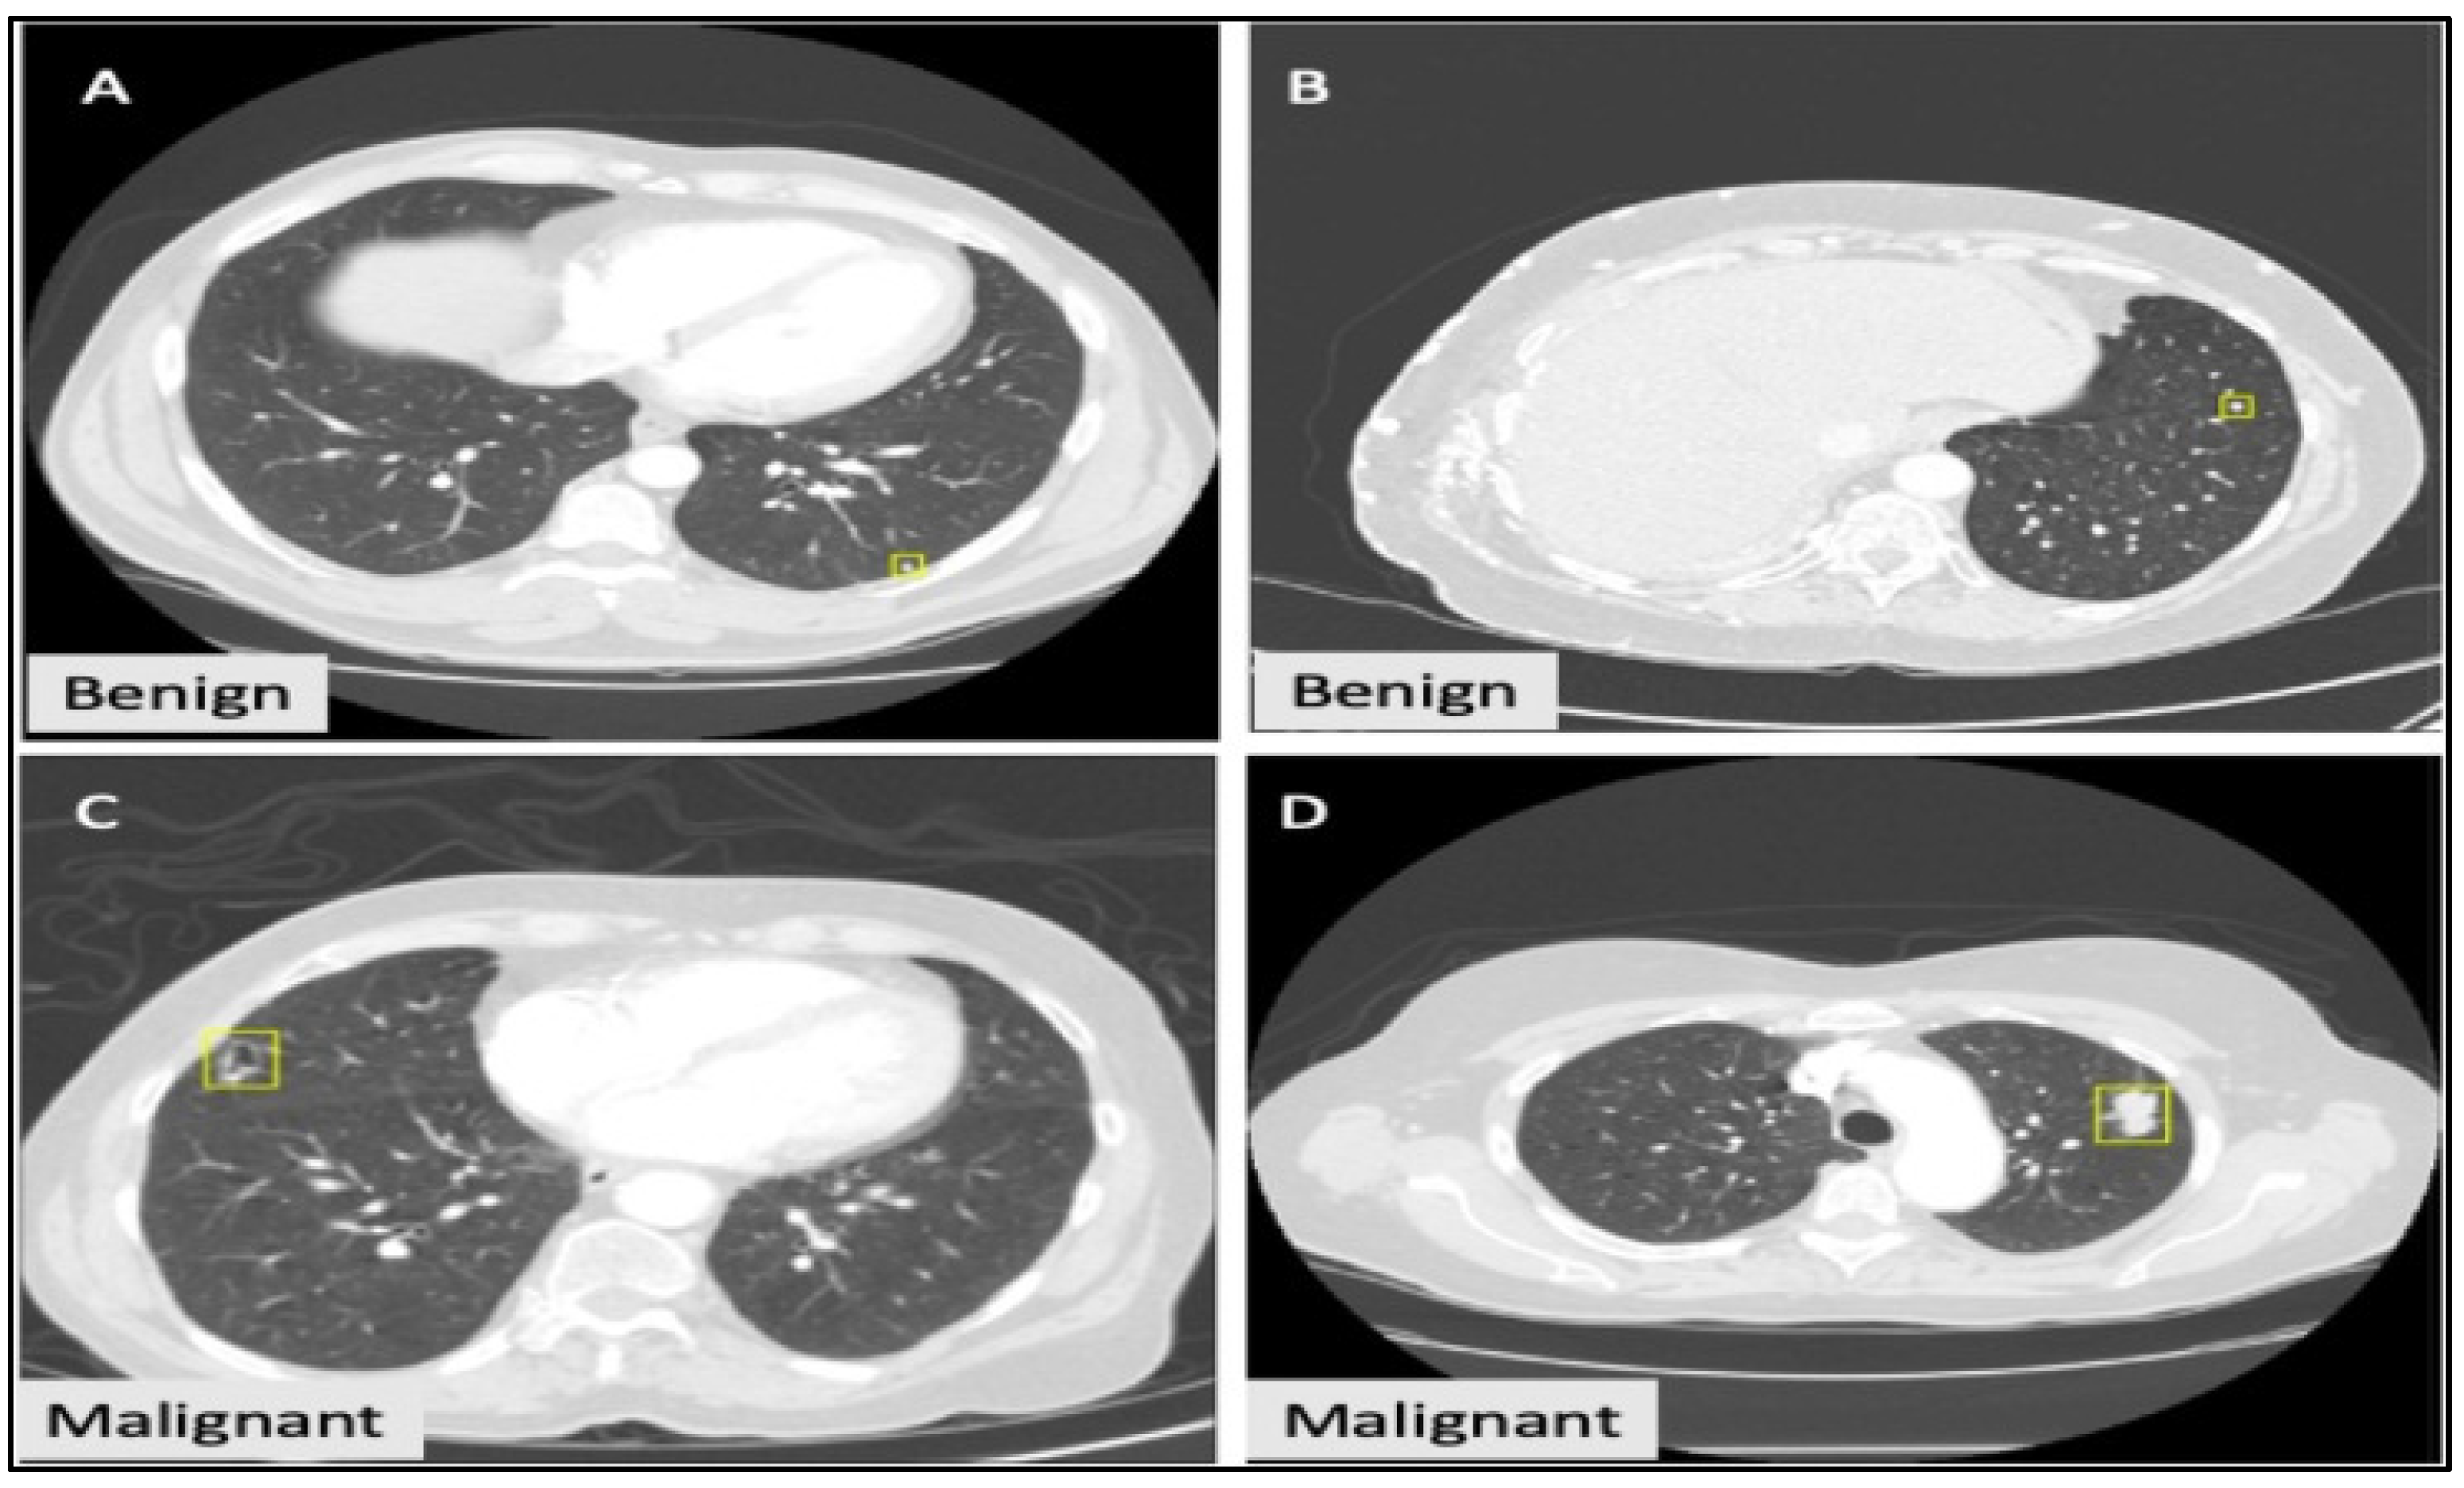

(ii) LIDC-IDRI Dataset

The LIDC-IDRI dataset is the world’s biggest publicly available database for researchers and consists of thoracic CT images (1018 CT scan images) from 1010 patients (Figure 6). These images show the presence of lung cancers and nodule annotations, which means outlines. The nodule annotations are available for all patients. Still, the diagnostic information is presented for 157 patients, which consists of nodule information ratings, where 0 is an unknown class, 1 is the benign class, 2 is the primary malignant class, and 3 is the metastatic (malignant) class.

Lung classification results.

The ratings assigned for each image are based on a biopsy, surgical resection, progression, and the revision of radiological images. The diagnosis class is classified into two classes: (i) patient level and (ii) nodule level. To make this dataset for radiologists, images from 1000 patients were obtained over a long time with different CT scanners. We present the diameter size distribution for lung nodules in the LIDC-IDRI database in Table 6. Multiple lung nodules accompany the different slices. Each lung nodule slice comprises annotated data, and its presence is based on a 3 mm size.

In the LIDC database, diagnostic data are the means of ascertaining malignancy. We chose the ratings from diagnostic data; the ground truth was processed for training in the triplet CBMIR system, and it was evaluated by comparing the results with the radiologist-given ratings in the database. This database provides annotations for nodules with sizes from 3 mm to 30 mm shown in the yellow box.